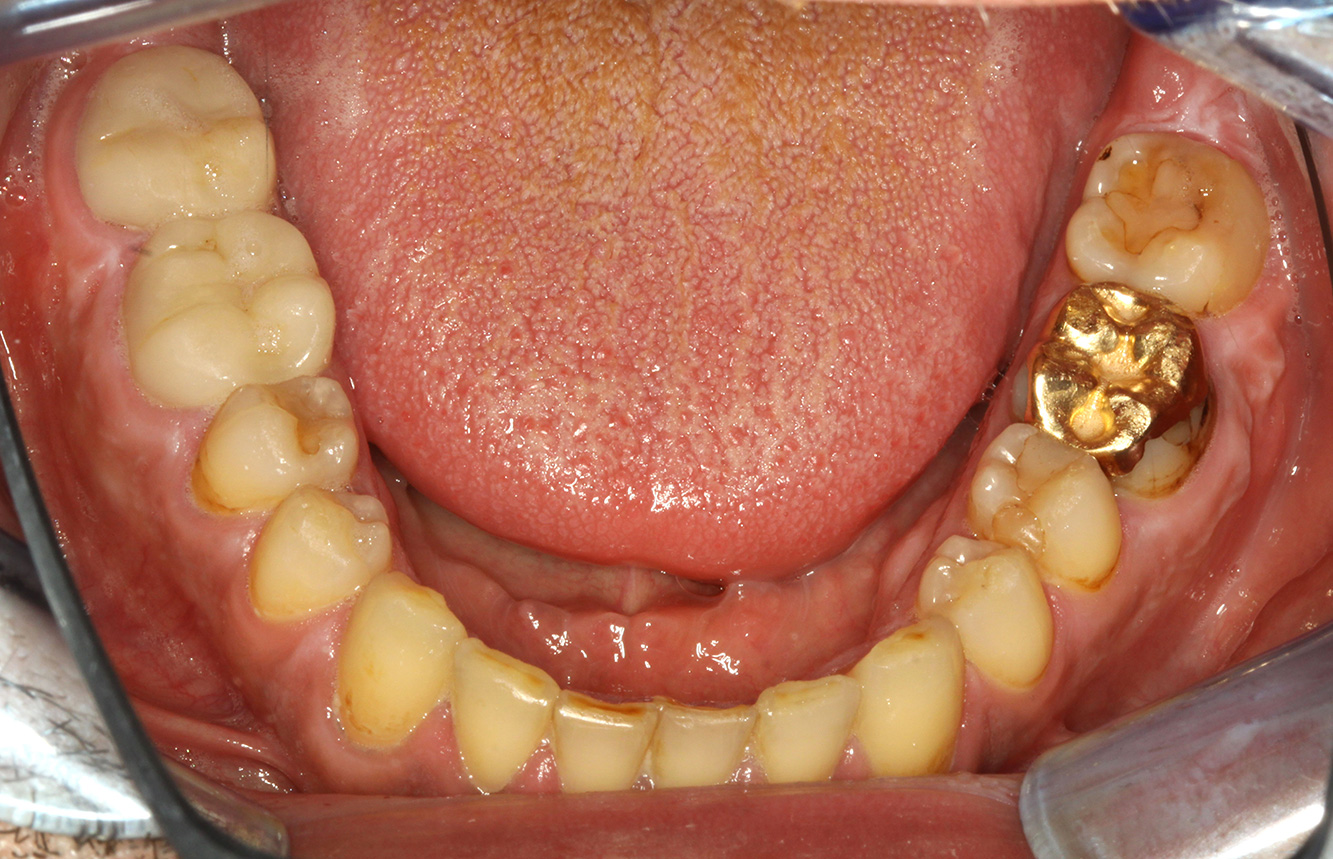

El paciente tiene 39 años con valvuloplastia frente a una insuficiencia valvular y endocarditis. Toma regularmente ASS 100 (ácido acetil salicílico) como anticoagulante. En el ámbito del estilo de vida, la alimentación se identifica como promotora de caries, ya que suele consumir alimentos azucarados y seis o siete comidas al día. La salud oral del paciente muestra un riesgo medio de caries con lesiones activas. El riesgo de periodontitis es bajo, presenta gingivitis. Se hacen las siguientes recomendaciones para el tratamiento profiláctico.

Para la sesión de profilaxis no hay recomendaciones específicas de instrumental. Mediante el uso dirigido de un aeropulidor y del pulido rotativo, puede eliminarse suavemente la placa y la decoloración en los bordes de la restauración y reducirse los nichos de recolonización para bacterias carcinógenas (19).

Para prevenir aún más las caries, se recomienda la fluoridación, especialmente para prevenir la nueva formación en el área de los márgenes de restauración y para sellar las superficies radiculares. Ambas medidas pueden reducir la sensibilidad a la temperatura de los dientes.

Debido a las lesiones de caries activas y el riesgo de progresión asociado, hay un intervalo de control posterior más corto, de cuatro meses.